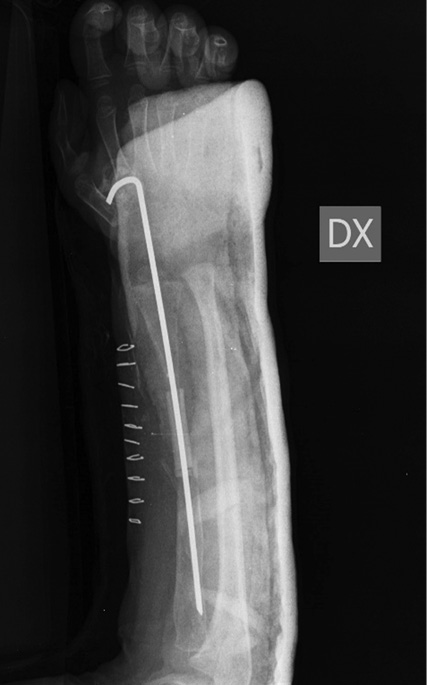

Через 10 дней после выписки из больницы пациент вновь обратился в отделение неотложной помощи с нарастающей болью в ноге, откуда была получена кость. Установлен диагноз местной гематомы, вызванной поражением межкостной артерии. В связи с этим проведена экстренная сосудистая операция для дренирования гематомы и закрытия поражения артерии. В феврале 2016 г., всего через 10 дней после последней операции, у пациента снова появилась боль в ноге. Было решено обратиться за советом в другой институт, в котором диагностировали псевдоаневризму пораженной артерии, по поводу которой проведена новая экстренная сосудистая операция. Между тем рентген не показал консолидации трансплантата в предплечье. После неудачи повторного введения факторов роста костного мозга в декабре 2016 г. выполнена новая операция с санацией очага несращения и трансплантацией трупной кости с фактором роста костного мозга, стабилизированной спицами Киршнера (рис. 5, 6).

Рис. 5. Отсутствие на рентгенограмме консолидации аутологичной малоберцовой кости

Рис. 6. Рентгенограмма после санации очага несращения и трупный костный трансплантат с костномозговым фактором роста, стабилизированный спицами Киршнера